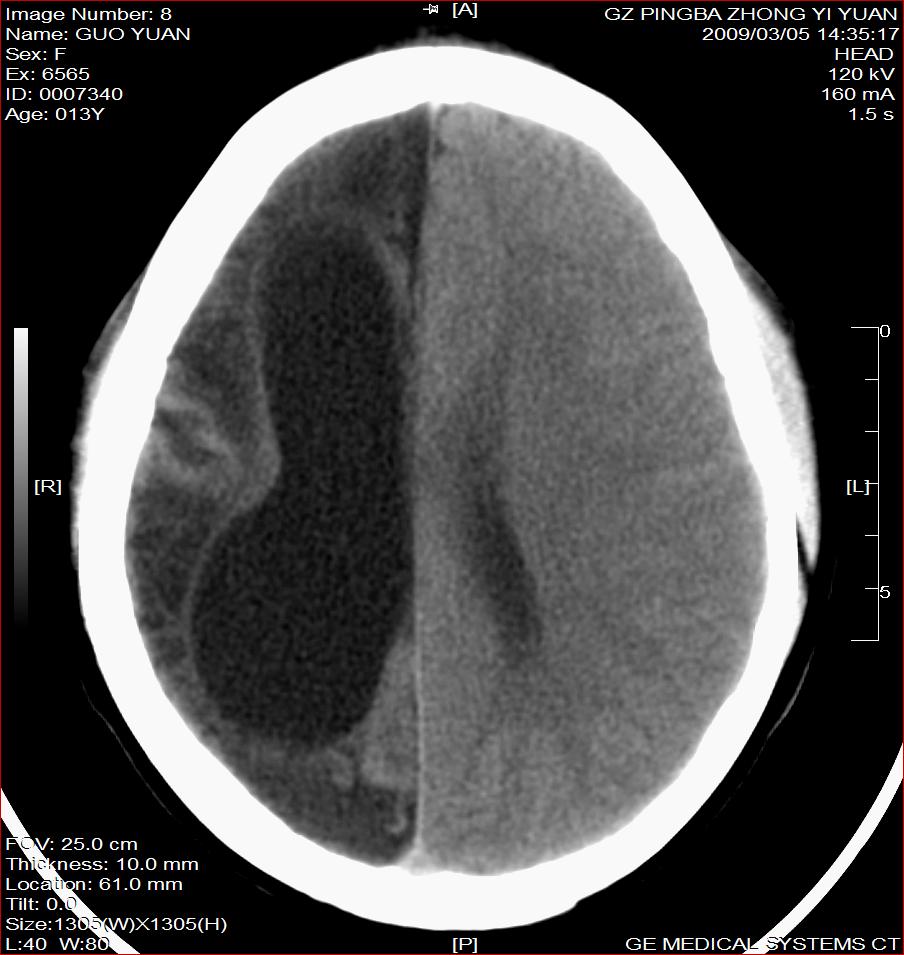

以下是引用杀毒软件在2009-3-6 17:32:00的发言:[br]右侧额颞顶部脑沟裂增宽,颞顶部楔形稍低密度影,侧脑室体部明显增宽,余脑实质内未见异常,中线结构居中。[br][br]考虑---右侧大脑半球发育不良并脑沟裂发育畸型可能性大

以下是引用随光逐影在2009-3-6 18:35:00的发言:[br]1)考虑右侧幕上半球发育不良并脑软化灶。2)双侧额部头皮软组织肿胀。